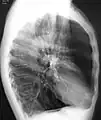

A lateral chest X-ray of a person with emphysema, displaying barrel chest and flat diaphragm